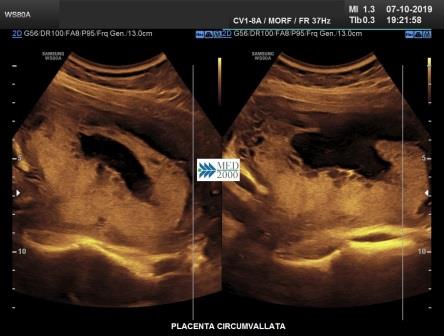

Placenta circumvallata è una patologia che si verifica in circa l' 1% di tutte le gravidanze, dovuta probabilmente ad un impianto più profondo della placenta nella decidua che comporta una discrepanza tra dimensioni del piatto coriale e la base di impianto della placenta. Di conseguenza le membrane corioamniotiche non si inseriscono sul bordo della placenta ma più verso il centro ripiegando su se stesse fino a formare il caratteristico margine circonferenziale arrotolato "tipo cornicione della pizza". Ecograficamente il margine placentare arrotolato che si estende tra i due margini placentari appena al disopra della superficie della placenta appare come una spessa area lineare di echi che attraversa la superficie della placenta assumendo, in sezione trasversa, un "aspetto a mensola". Tale aspetto può simulare una sinechia ma a differenza della placenta circumvallata la sinechia si estende in senso antero-posteriore attraverso la cavità uterina e non ha alcuna relazione con la posizione della placenta, elementi questi che consentono di porre una corretta diagnosi differenziale. La placenta circumvallata può associarsi ad una più alta incidenza di complicanze perinatali come la nascita pretermine, rottura prematura delle membrane (PROM), distacco di placenta.